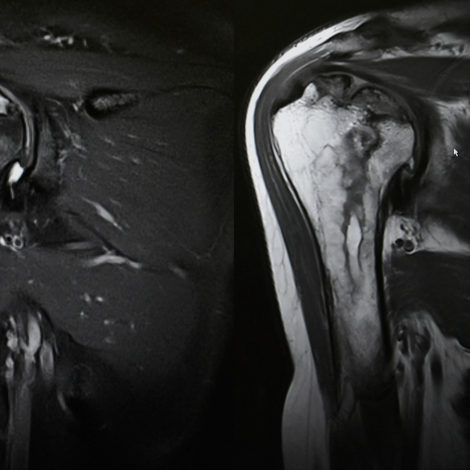

Shoulder MRI

MRI of the shoulder is typically performed to diagnose or evaluate: Degenerative joint disorders such as arthritis and labral tears, fractures, rotator cuff disorders, joint abnormalities due to trauma, sports-related injuries, infections, tumors, unexplained shoulder pain that does not get better with treatment, decreased motion of the shoulder joint, to evaluate progress after shoulder surgery.